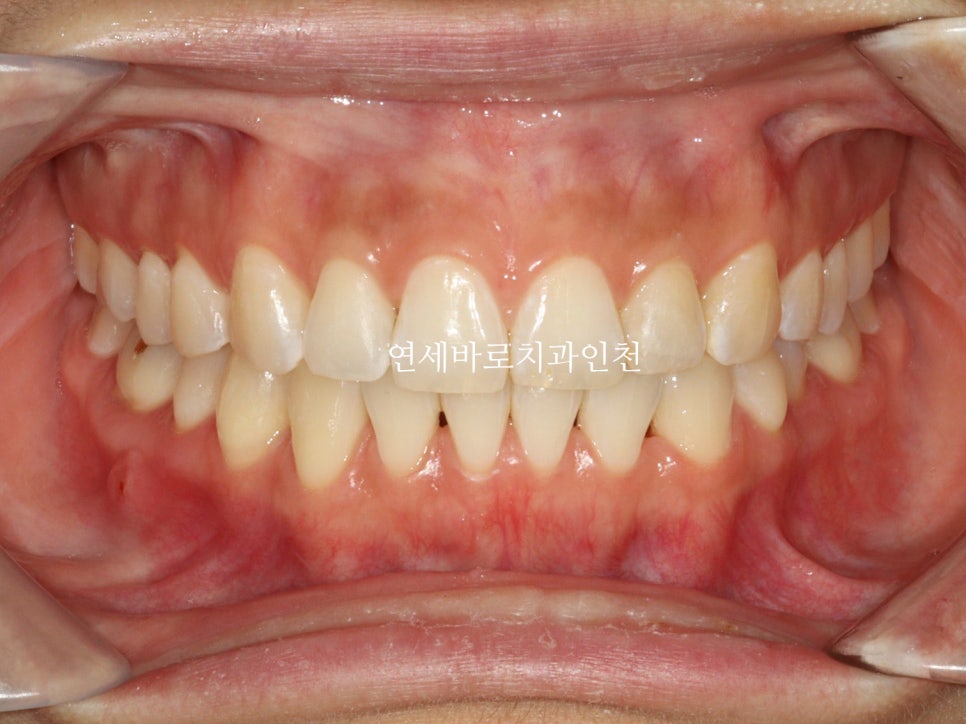

치열이 삐뚤삐뚤하신 상태입니다.

치열의 배열 및 골격적인 분석 결과 무턱과 입술이 자연스럽게 다물어 지지 않는 것도 발견되었습니다.

교정이 마무리되고 보면 문제없죠?

전후 측면 모습입니다.

치아가 확실히 후방이동을 하며 배열되었습니다.

조금 더 자연스러운 입술의 위치를 확인할 수 있었습니다.